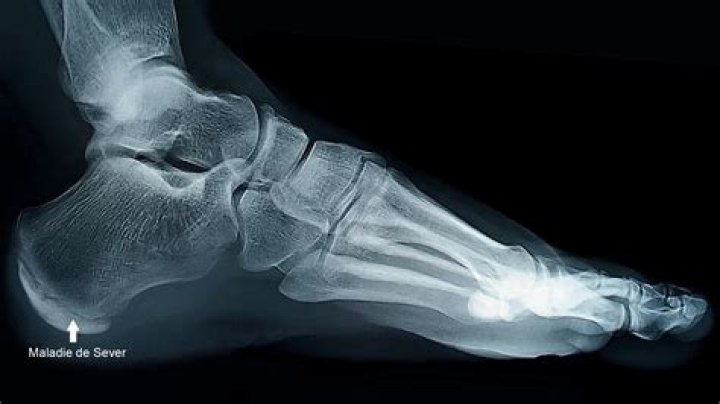

L’os naviculaire, qui se situe entre le talus et les os cunéiformes à l’arrière du pied, est affecté par cette affection. Pour des raisons inconnues, cet os perd sa vascularisation et se nécrose”, explique Denis Mainard, président de l’Association française de chirurgie du pied et chef du service de chirurgie orthopédique à l’hôpital de Nancy.

Les symptômes du syndrome de Müller-Weiss, une maladie rare qui affecte un os du pied, comprennent une gêne et un gonflement chroniques. L’ostéonécrose de l’os naviculaire (ou scaphoïde tarsien), également connue sous le nom de maladie de Müller-Weiss, afflige le Majorquin depuis l’âge de 18 ans.

Il l’a décrite comme une maladie dégénérative “chronique et incurable” début mai. L’os naviculaire, entre le talus (anciennement appelé astragale) et les os cunéiformes, est touché par ce syndrome.

Comme l’explique Denis Mainard, chirurgien orthopédique et président de l’Association française de chirurgie du pied, “Cet os est soumis à des contraintes importantes et pour des raisons que nous ignorons perd sa vascularisation et se nécrose”. L’hôpital de Nancy.